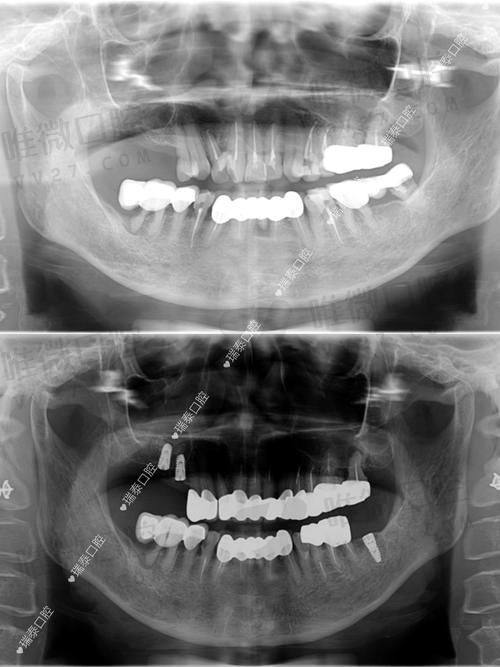

特别多人问:“我跟别人长得差不多,为什么他种牙比我便宜?”其实这是误解。种植牙是高度个性化的医疗项目,需要结合骨质密度、牙槽结构、邻牙稳定性等多维度判断,费用自然有所区差。

举个例子,同样用ITI种植体,A同学年轻牙槽骨好,不需植骨,3980元起特别稳。B叔骨骼条件需要先植骨、做引导,再等愈合种牙,那可就得上7000-8000了。价格差异是对复杂程度的体现,不是“谁被坑了”。